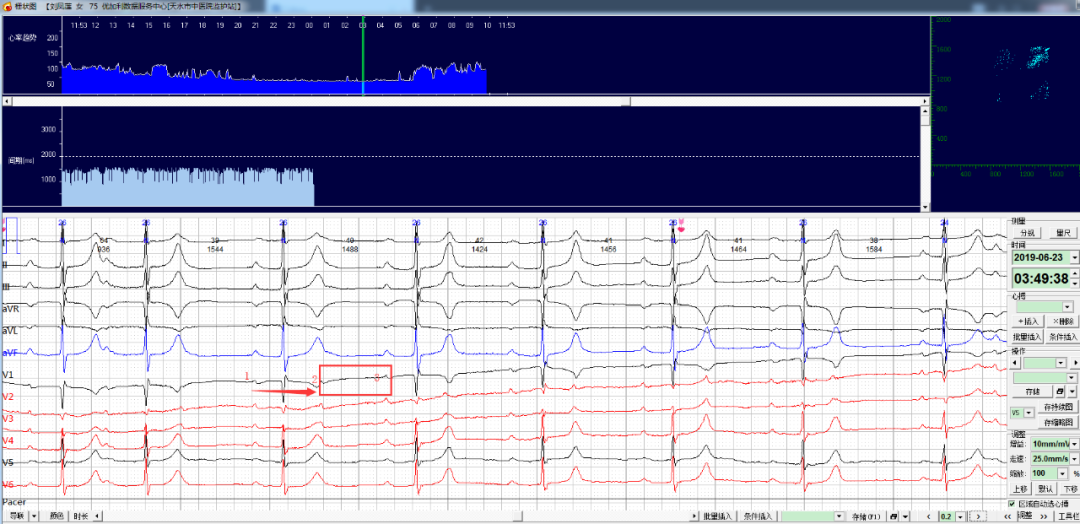

每日一圖丨NO.659 通過以下兩幅心電圖診斷患者出現(xiàn)了什么異常呢?

今日讀圖(NO.659)

患者張某,男性,68, 病史不詳;

佩戴心安寶動(dòng)態(tài)心電監(jiān)護(hù)儀,監(jiān)測到如下片段如何分析診斷?